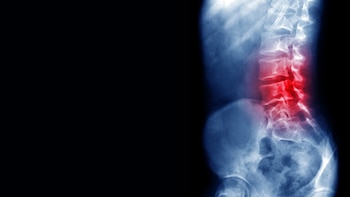

Como ustedes pueden ver, también el disco puede sufrir transformaciones. Se puede romper, se puede correr y ahí, en lo que en el video se aprecia como una zona roja es cuando se produce una inflamación, que ocurre cuando se comprime un nervio a la salida de la médula, cuando pasa entre las vértebras. Eso puede deberse a un golpe, a una mala postura, a que se corrió una de las vértebras, o a osteoporosis, entre otras dolencias.